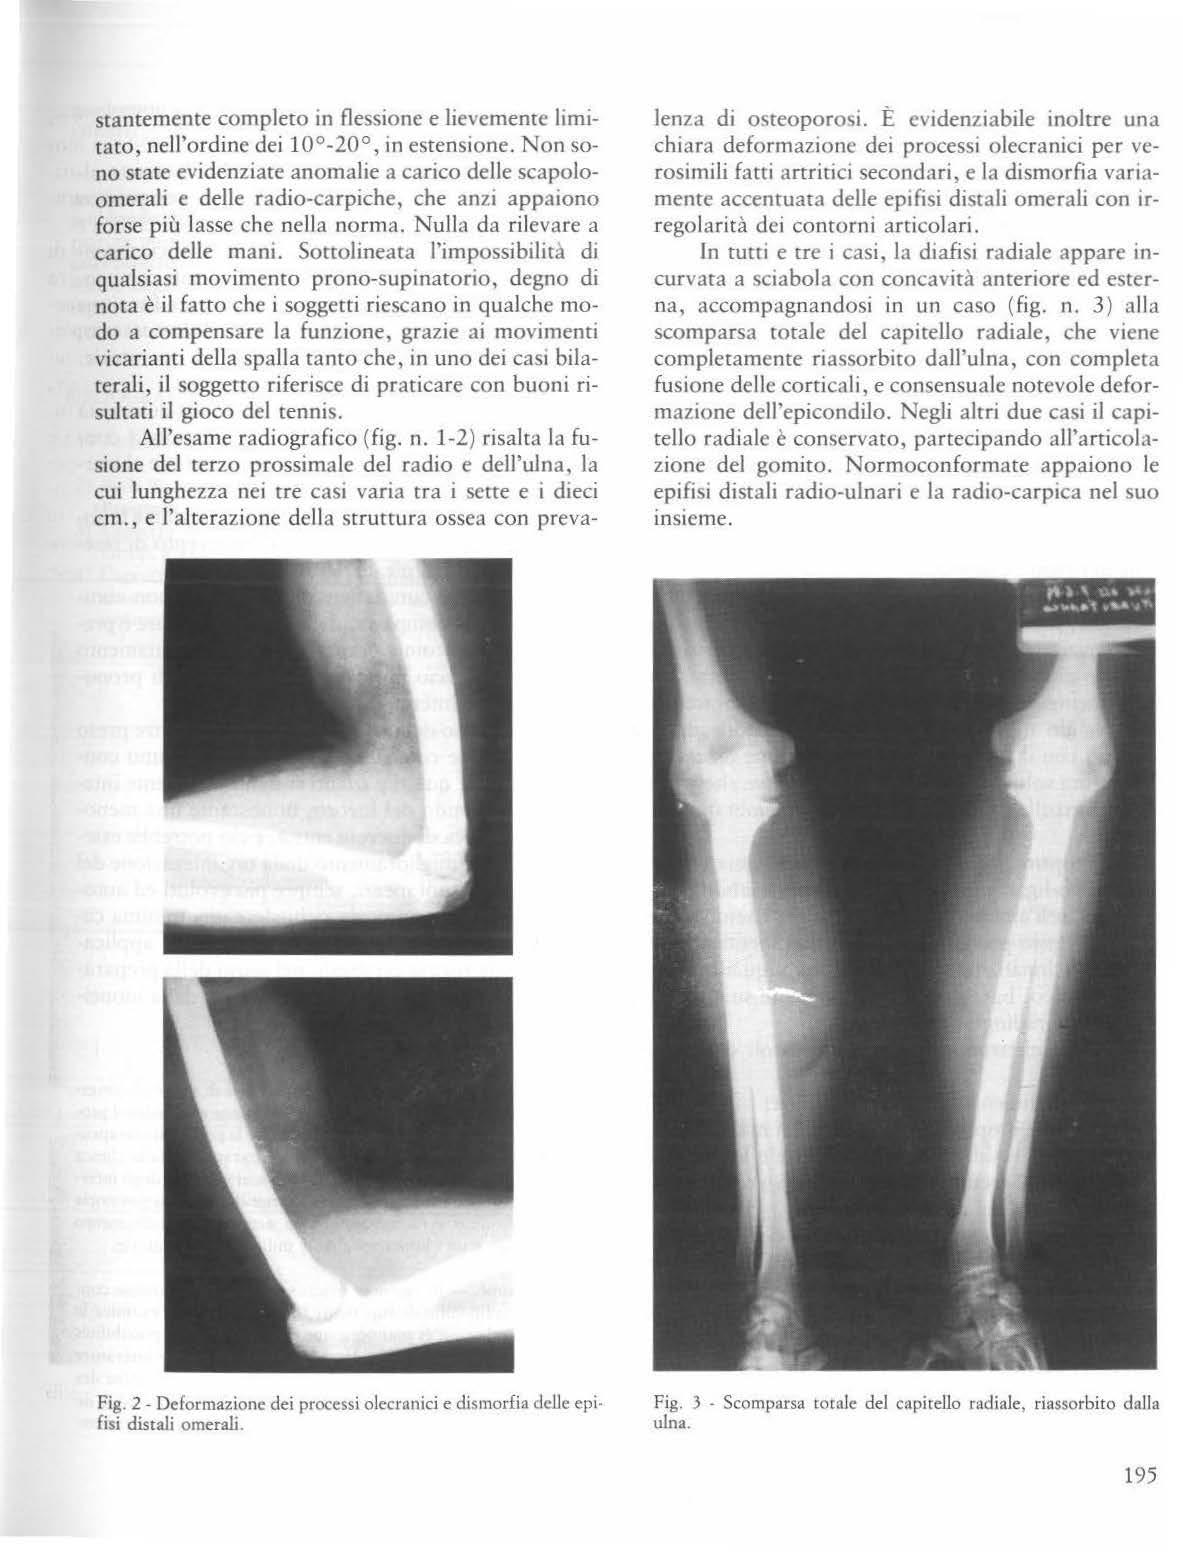

9) Froug C. «.Liposarco ma of kidney: review of literarure and case report» J. Urol. 45, 290, 1941.

10) Gallagher J.C., Winslow D.J., Grossman A. «Coexisrenc chondrosarcoma and transitional cell carcinoma in the kidney» Urology 3, 473, 1974

11) Granmayeh M. , Wallace S., Barrett A.F. , Fisher R., Heslep J.H. «Sarcoma of the kidney: angiographic features» Amer. J. Rocntgenol. 129, 107, 1977.

12) Hajdu S.l., Foote F.W. Jr <<Angiomyolipoma of the kidney: report of 27 cases and review of rhe lirerature>> J Uro!. 102, 396, 1969

13) Hahn F.J.Y., Schapiro R.L. «Rctroperitoneal fibroxa nthosarcoma: report of a case» J. Uro!. 116, 667, 1976.

14) Judd E.S., Donald J.M . «Sarcomas of che kidney of the adult. A riview of 20 cases wirh a report of a case,} Ann. Surg. 96, 1028, 193 2.